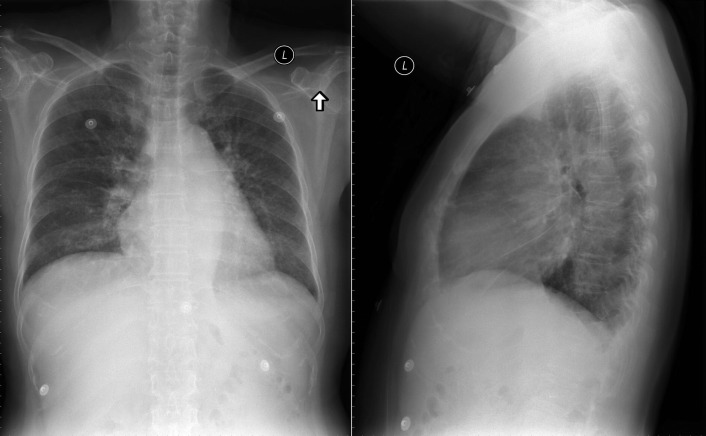

The radiographic findings of mitral stenosis ( Graphic 15-1 ; Figs. 15-1 to 15-16 ) reflect the pressure overload of the left atrium and pulmonary veins, and later of the right heart. As well, the commonly associated chronic atrial fibrillation contributes to (bi)atrial dilation. Associated rheumatic valvular lesions such as mitral regurgitation, tricuspid regurgitation, aortic insufficiency, and aortic stenosis/aortic insufficiency are common, and they alter the appearance of the heart.